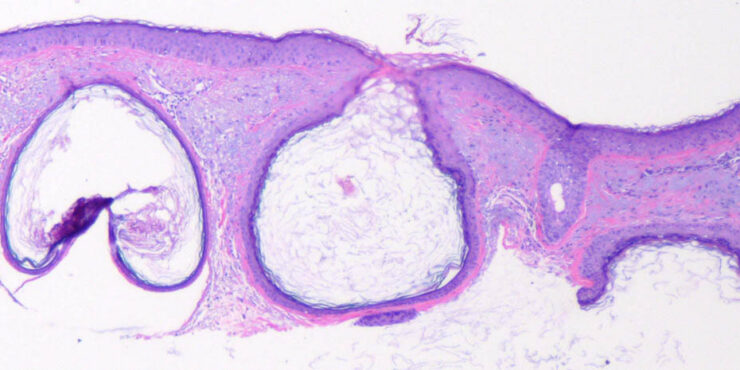

Read MoreClear Cell Acanthoma Degos =الشوكوم رائق الخلايا لديغوس OLYMPUS DIGITAL CAMERA OLYMPUS DIGITAL CAMERA OLYMPUS DIGITAL CAMERA OLYMPUS DIGITAL CAMERA Clear Cell Acanthoma Clear cell acanthoma, a tumor that is clinically and histologically quite distinct, was first described in 1962 (122). It is not rare. Typically the lesions are solitary and occur on the […]